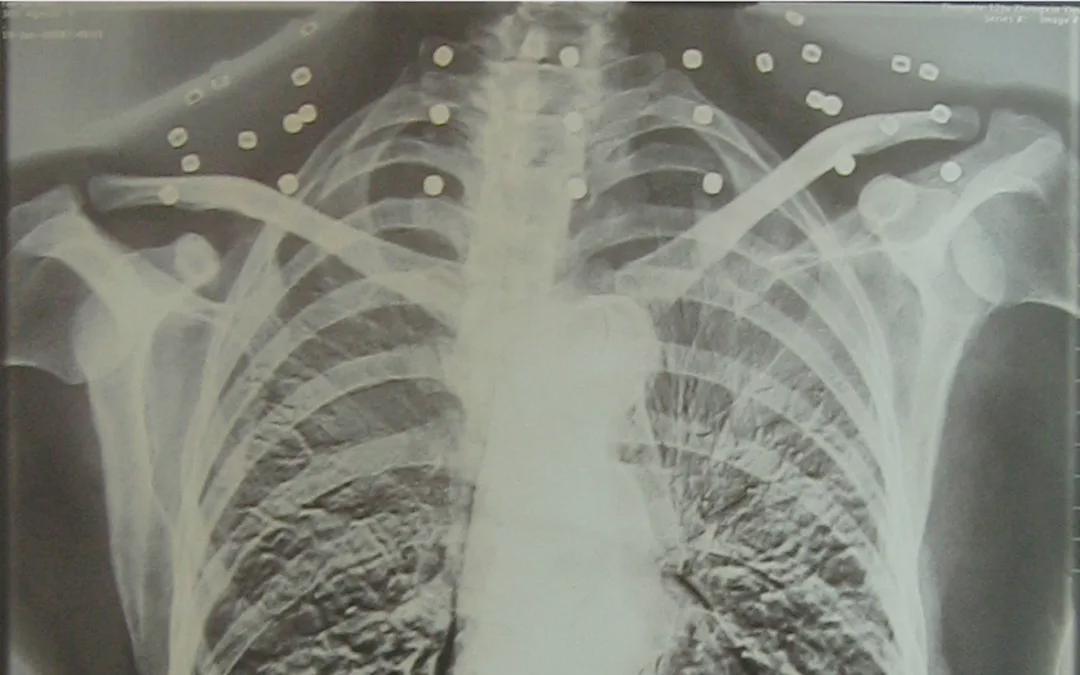

这张照片,是今年82岁的吴以先老人拍摄的一张CT照。

20年前,吴以先在一次做CT检查时,医生误以为他戴了项链,提醒他取下再做检查。然而,事实是吴以先的颈部和腹部,共分布着33枚弹片。这段无意间的对话,揭开了吴以先老人一段不平凡的往事。

后来虽然伤势好转,但是吴以先的右手落下了残疾,直到现在他体内的弹片都没有取出每到天气变化时身体留有弹片的位置就有痛感

但吴以先不考虑取出弹片,在他看来,这是他与战友并肩作战的见证,是他的勋章。

岁月虽逝,硝烟散去,但那份军人的荣耀与担当,与吴以先身上那33枚弹片一起,永远烙印在他心中。

33枚“军功章”,是一名军人的光荣,也是一位英雄的至诚本色。